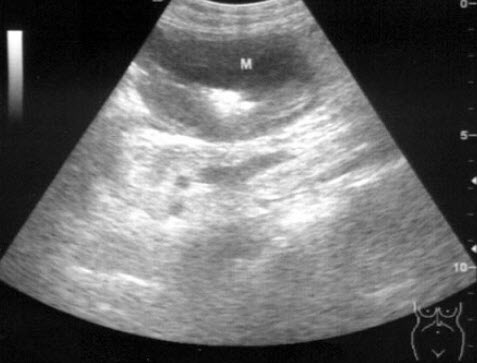

9、单项选择题

男,有胃癌手术史。根据超声声像图诊断为()

A.脾梗死

B.脾淋巴肉瘤

C.脾错构瘤

D.脾转移性癌

E.脾血管瘤